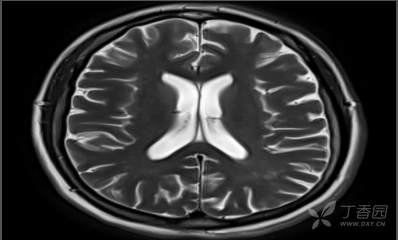

颈部、脑部动脉均未见明显异常,MRI+MRA+T2Flair+SWI+冠状位: 双侧额顶叶皮层下散在小缺血灶;双 侧海马萎缩2级,小脑蚓部、右侧额 叶微出血灶,如下图所示: